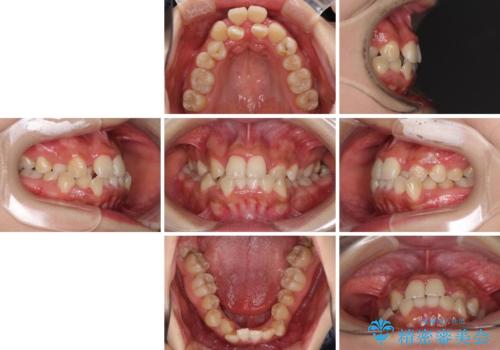

前後に重なった前歯 ワイヤー装置と急速拡大装置を併用したインビザライン矯正

- 前歯の著しい叢生とクロスバイトを気にして来院された患者様です。

叢生が強いため、一見すると抜歯矯正と判断したくなりますが、下顎臼歯が舌側に倒れていることから、上顎骨を側方拡大し、非抜歯矯正の可能性を検討することとしました。

非抜歯矯正が可能となった場合には、インビザラインにて矯正治療を行うこととしました。

急速拡大装置による上顎骨の側方拡大が思った以上にうまくいき、非抜歯での矯正が可能となりました。

内側に倒れていた下顎の臼歯は起き上がり、清掃性も大幅に改善されました。